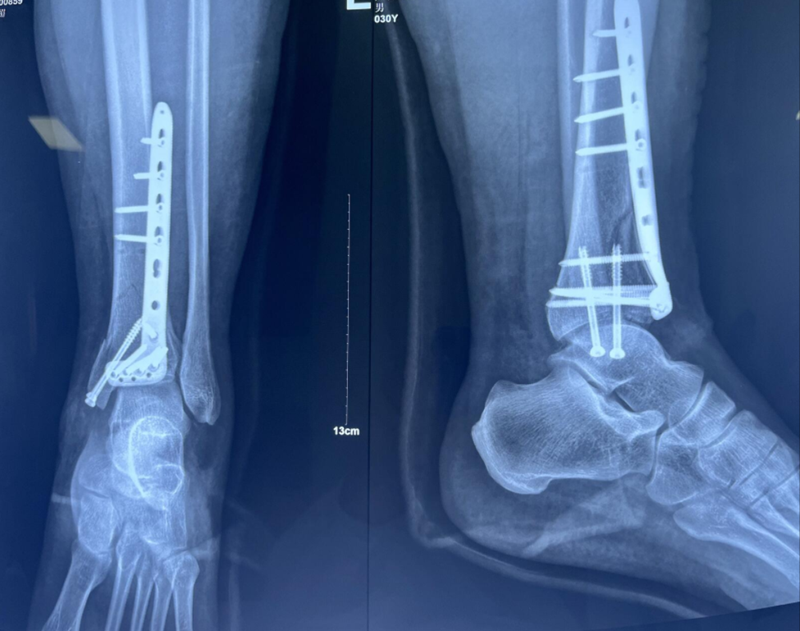

术后影像学资料:

诊断:左胫骨平台后柱骨折,后交叉韧带撕脱骨折,左踝关节pilon骨折3型。

图8 Pilon骨折3型